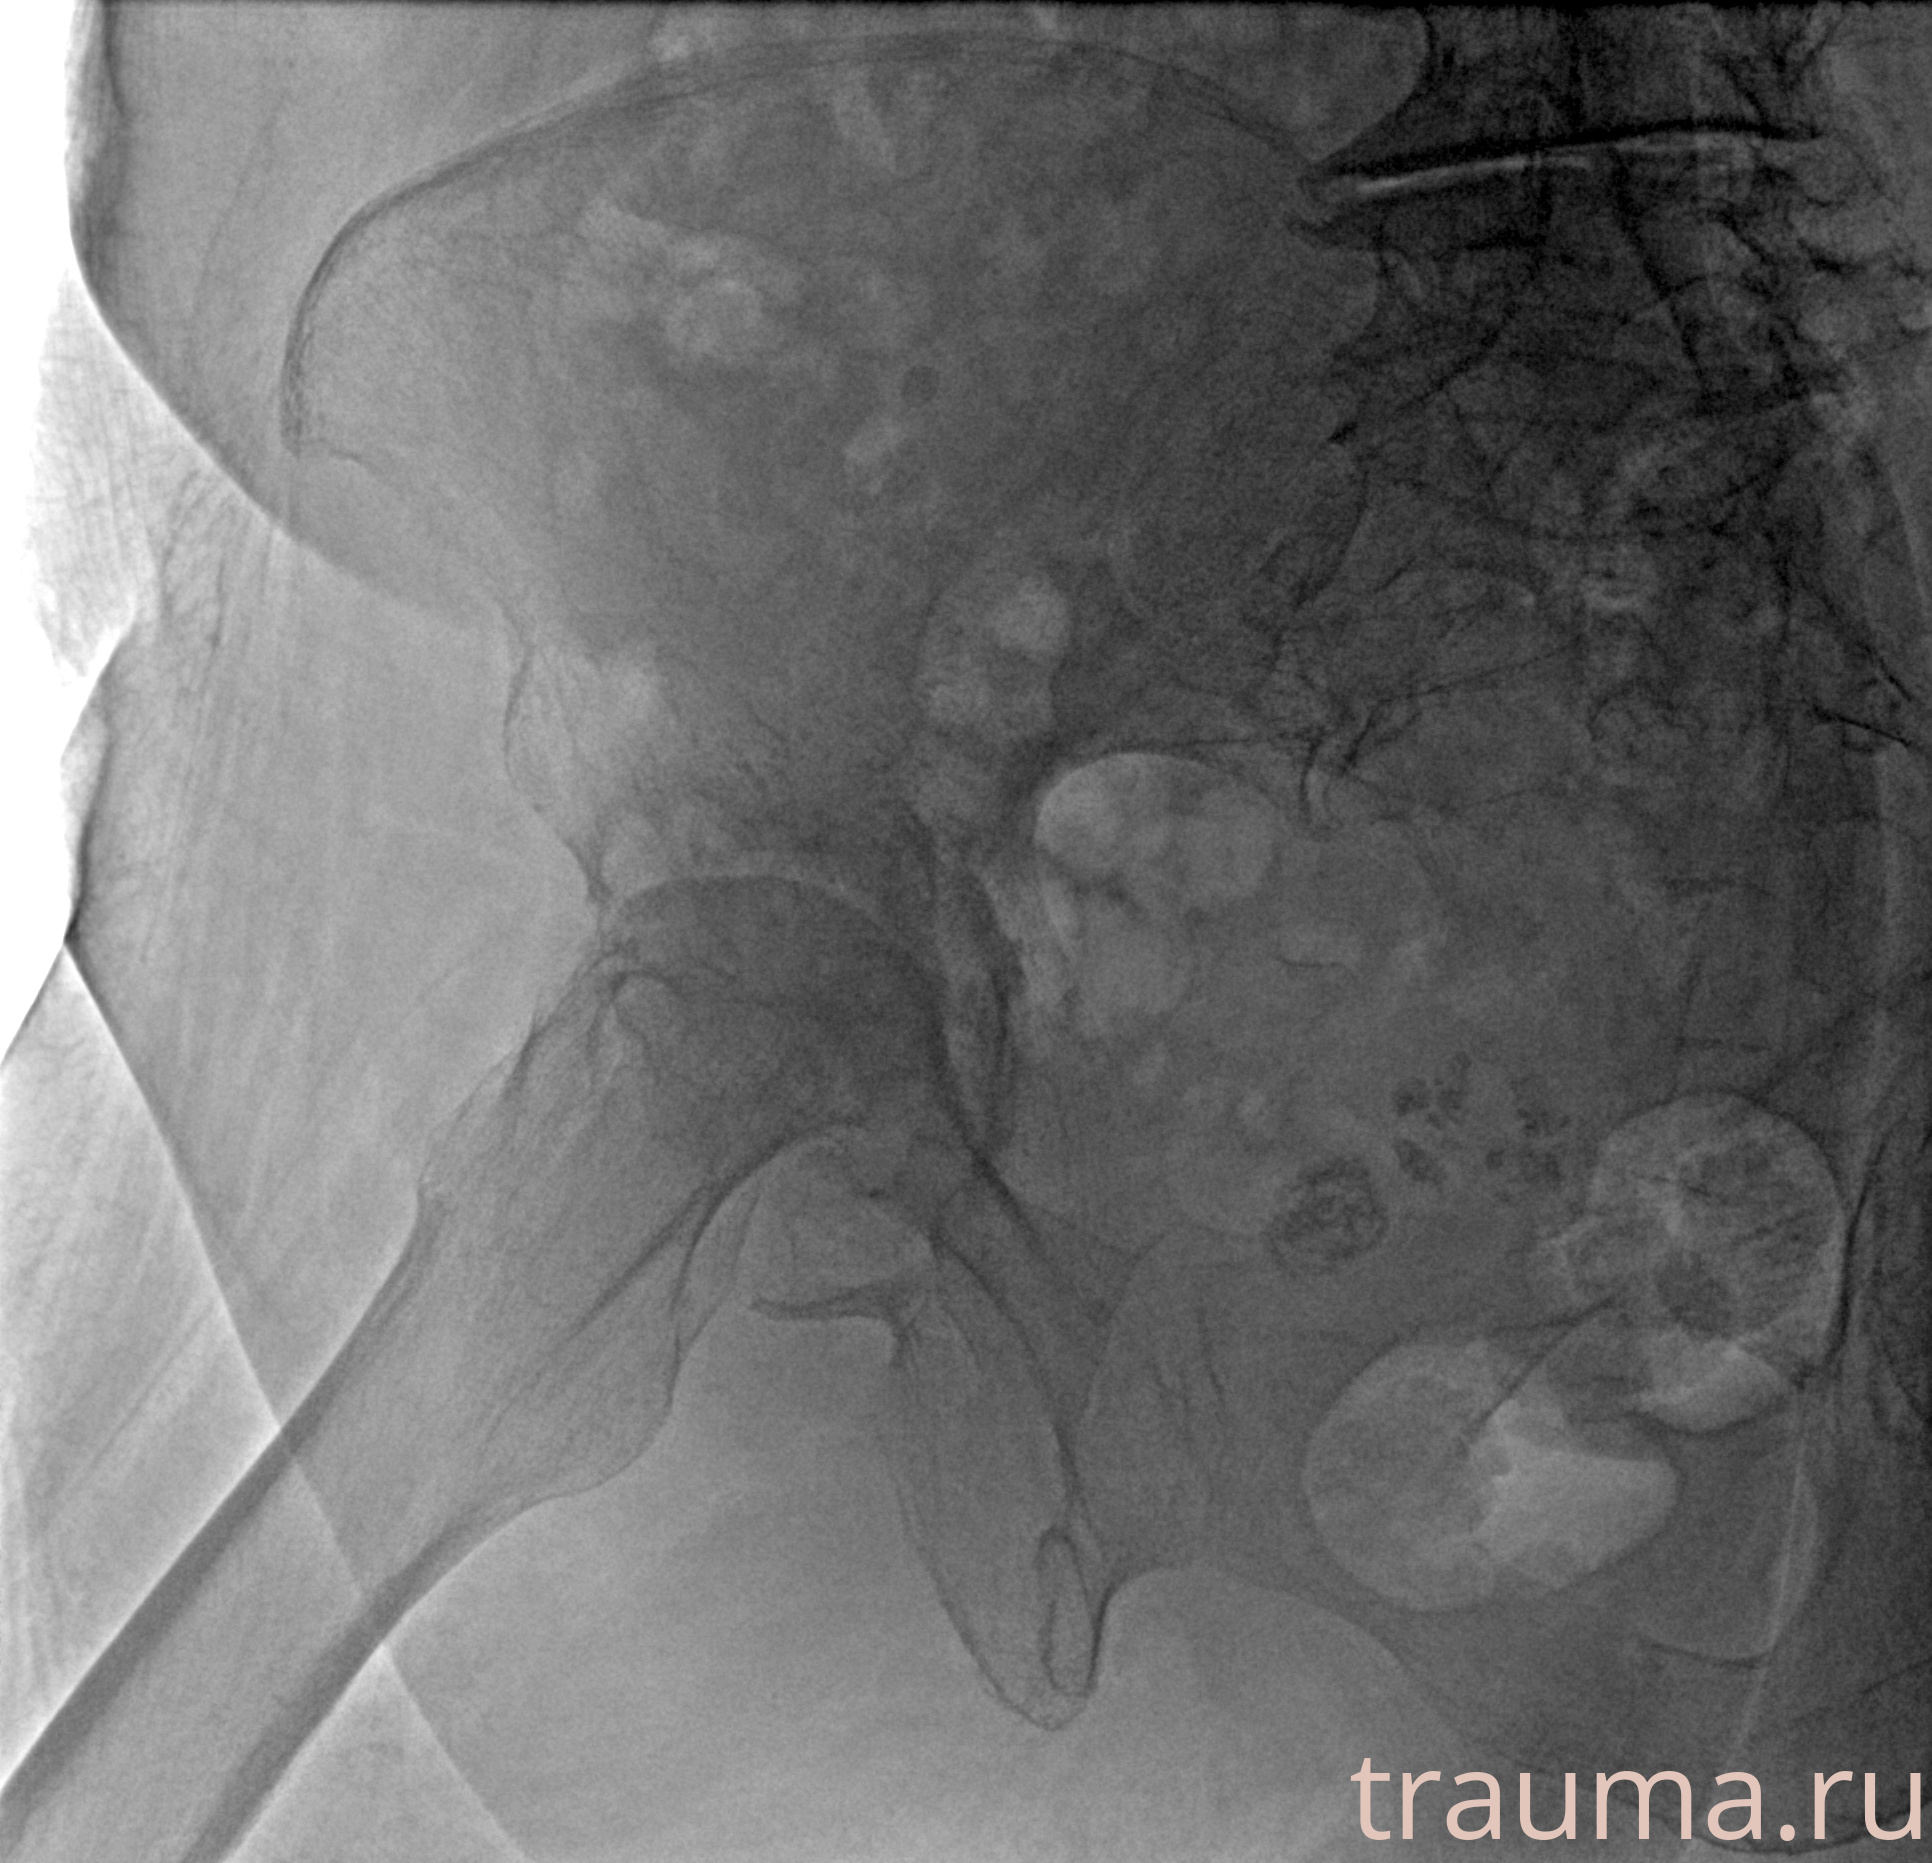

Рентген на дому: по вашему адресу приезжает врач-рентгенолог, травматолог-ортопед с мобильным рентгеновским аппаратом, проводит диагностику травмы или заболевания, делает необходимые рентгенограммы, дает рекомендации по дальнейшему лечению. Получить качественные снимки в домашних условиях возможно благодаря уникальной методике, разработанной МосРентген Центром для института  Склифосовского